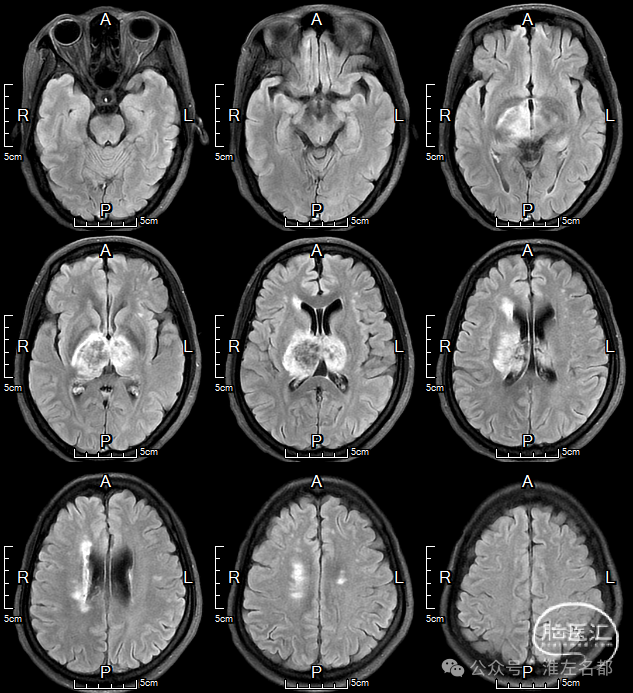

颅脑MRI

2024-9-25

FLAIR

双侧丘脑和右侧内囊-间脑淤血性梗死、水肿和伴渗血。

增强MRV:左侧横窦-乙状窦显影纤细;上矢状窦和右侧横窦-乙状窦充盈缺损;脑深部静脉和直窦未见显影。

SWI:双侧丘脑渗血改变,右侧基底静脉和大脑中静脉血栓。